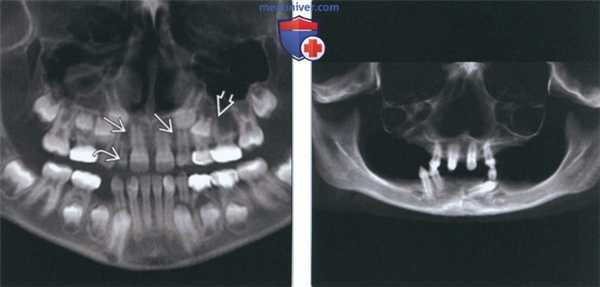

(Слева) На панорамной реформатированной КЛКТ визуализируется сохраненный временный второй моляр нижней челюсти слева. Постоянный второй моляр отсутствует; определяется низкое положение и анкилоз временного зуба (частое осложнение).

(Справа) На кадрированной панорамной рентгенограмме определяется отсутствие левого бокового резца верхней челюсти. Отсутствие бокового резца -часто встречающаяся ситуация.

(Слева) На панорамной реформатированной КЛКТ у восьмилетнего ребенка со смешанным прикусом определяется отсутствие постоянных боковых резцов и второго левого премоляра в верхней челюсти и их фолликулов. Обратите внимание на сохранившийся временный боковой резерв.

(Справа) На панорамной реформатированной КЛКТ у девочки 12 лет с эктодермальной дисплазией определяется олигодонтия с характерным «заострением» зубов. У пациентки также отсутствуют потовые железы и наблюдаются патологические изменения волос.